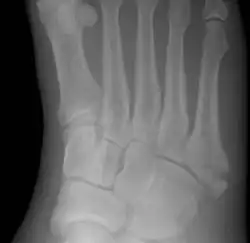

A Jones fracture is a broken bone in a specific part of the fifth metatarsal of the foot between the base and middle part .[8] In general, fifth metatarsal fractures heal readily, but a Jones fracture must be recognized and accurately diagnosed because of its higher rate of delayed healing or nonunion.[4] It results in pain near the midportion of the foot on the outside.[2] There may also be bruising and difficulty walking.[3] Onset is generally sudden.[4]

The fracture typically occurs when the toes are pointed and the foot bends inwards.[6][2] This movement may occur when changing direction while the heel is off the ground such in dancing, tennis, or basketball.[9][10] Diagnosis is generally suspected based on symptoms and confirmed with X-rays.[3]

A person with a Jones fracture may not realize that a fracture has occurred. Diagnosis includes the palpation of an intact fibularis brevis tendon, and demonstration of local tenderness distal to the tuberosity of the fifth metatarsal, and localized over the shaft of the proximal metatarsal.

Diagnostic X-rays include anteroposterior, oblique, and lateral views and should be made with the foot in full flexion.